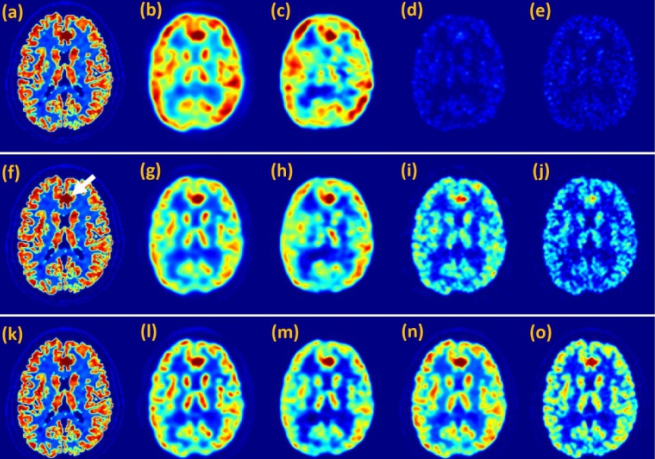

(a). The coherent image of a resolution chart is scattered by a rotating diffuser, and then the diffusive image is sent onto bulk NLCs. Nonlinear output from the NLCs is imaged onto a camera; (b). Coherent image; (c). diffusive image. (Image by XIOPM)